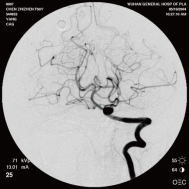

右侧颈内动脉后交通动脉瘤栓塞术前 左椎动脉造影 示左椎动脉夹层动脉瘤: 左椎动脉发出小脑后下动脉处呈囊性扩张,动脉瘤远端血管狭窄

颈内动脉创伤性假性动脉瘤覆膜支架治疗前后(三维像是术前) 右侧颈内动脉后交通动脉瘤栓塞术后完全闭塞

弹簧圈栓塞后造影示左椎动脉夹层动脉瘤消失, 左椎动脉、 多发动脉瘤夹闭术前、术中

左侧小脑后下动脉循环通畅